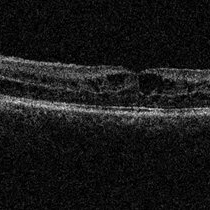

Best Disease Best DiseaseMar 9 2013 by Hamid Ahmadieh, MD OCT of the right eye of a 49-year-old man with decreased VA due to advanced Best disease. Photographer: Soodabeh Fooladin, Negah Eye Center, Tehran Imaging device: Heidelberg Spectralis Condition/keywords: Best disease, optical coherence tomography (OCT)